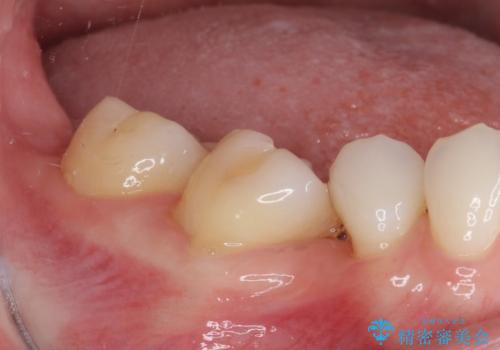

- 全体的なデコボコと、奥歯の欠損を放置した結果倒れ込んだ奥歯などを気にして来院された患者様です。

ワイヤー矯正の方が理想的な仕上がりとできる状態でしたが、上顎前歯にクラウンが装着されているため、インビザラインにて矯正治療を行うこととしました。

欠損部位は傾斜歯軸を起き上がらせることができたため、オールセラミッククブリッジにて補綴治療を行いました。